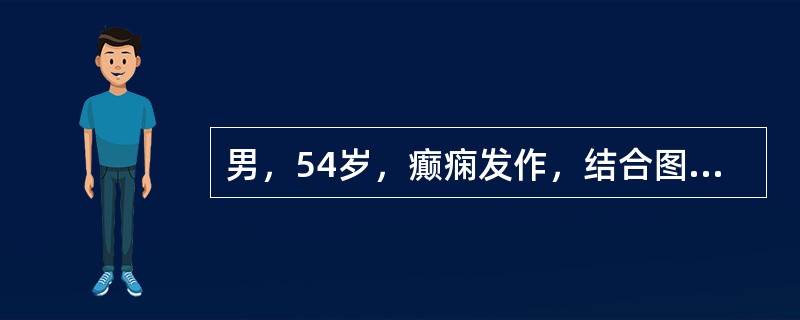

男,54岁,癫痫发作,结合图像,最可能的诊断是()

A.脑脓肿

B.脑出血

C.海绵状血管瘤

D.胶样囊肿

E.脑转移瘤